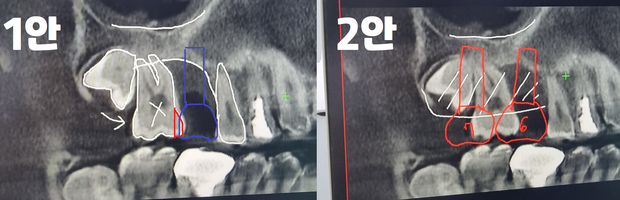

치아가 거의 없는상태로 지낸지 오래되어 사랑니가 7번어금니를 밀게되어 현재상태여서

7번 어금니,8번(사랑니) 치아를 제거후, 뼈이식을 진행한 다음 6,7번 어금니에 임플란트 하는쪽으로 진행해야한다고 말씀하시더라구요.

1안과 2안중 어떠한것이 나은지 여기계신 전문의분들에게 질의를 드립니다

• 2번 째 사진